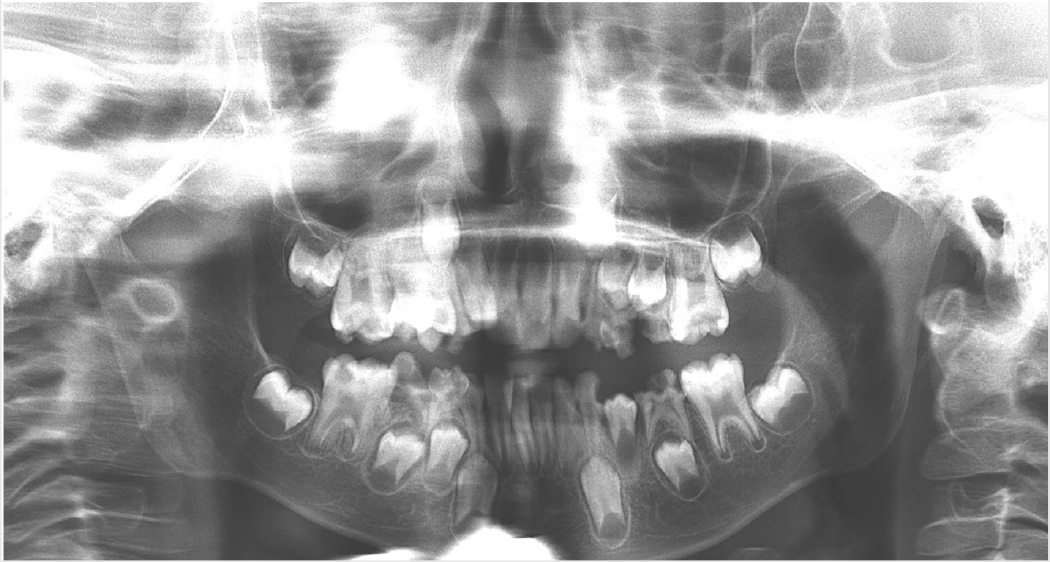

(PDF) Recent advances in dental radiography for pediatric patients A Dental Patient Case Report Dens invaginatus in paediatric dental patients. dens invaginatus and the paediatric dental patient: Previous issue | next issue. a case report is a structured report of the clinical process of a patient’s diagnostic pathway, including symptoms, signs,. this case report describes an interdisciplinary approach that took 7 years to successfully treat a young patient with. case. Dental Patient Case Report.